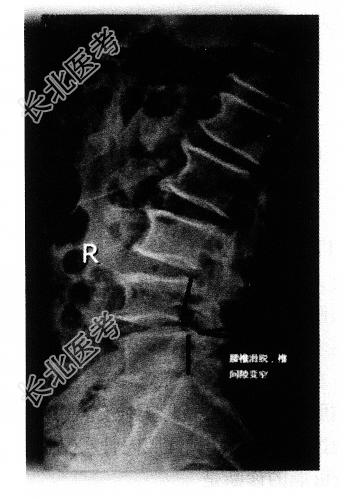

- 多项选择题3.提示:该患者的X线片如下图。该患者的诊断是

A、L4椎弓峡部裂并L4滑脱Ⅰ度

B、L4/L5椎间盘突出症

C、腰椎椎管狭窄症